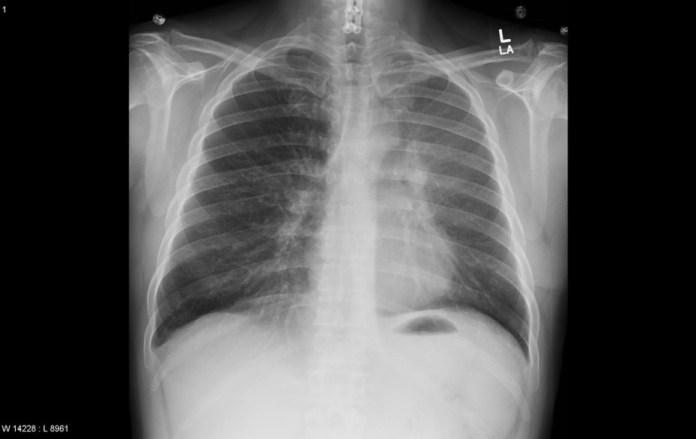

Diagnosis: Luftsichel sign – Luftsichel sign – Left upper lobe collapse

Modality: Frontal Chest X-ray